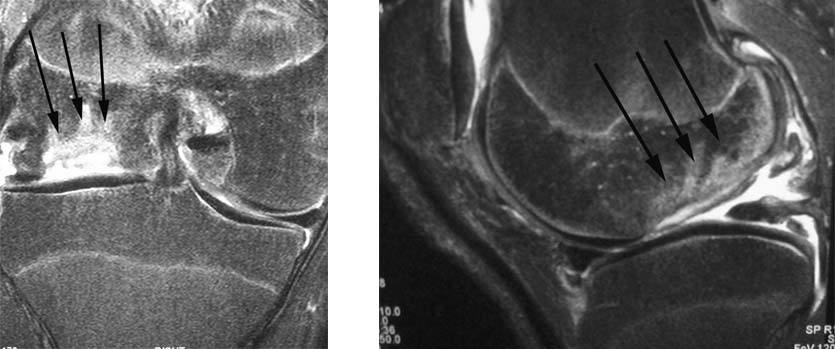

1.The standard radiographs of his knee shows an irregularity of the medial femoral condyle (black arrows).

2.This sagittal MRI image shows irregularity of the articular cartilage surfaces in the medial femoral condyle and medial tibial plateau (small white arrows). There is also bone edema (black arrow) noted in the femoral condyle consistent with early degenerative changes. The posterior horn of the medial meniscus appears normal (white arrowhead).

2.MRI images of the knee show a major cavitary defect within the lateral femoral condyle with absence of overlying cartilage.